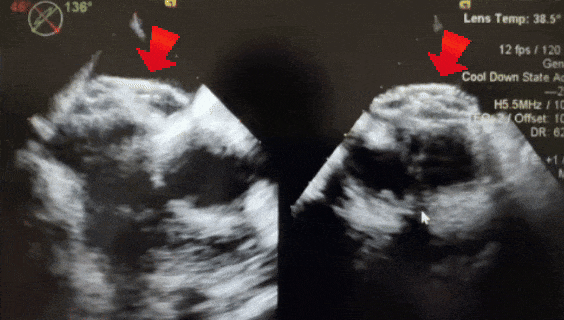

成型锁定

鞘管抵住封堵器后,前顶钢缆固定,牵拉成型线锁定

锁定后,超声下观察封堵器结构,盘面呈标准的三明治结构,成型良好

牵拉试验

轻轻推拉钢缆,超声下封堵器与钢缆整体移动,结构稳定无散开,锁定成功